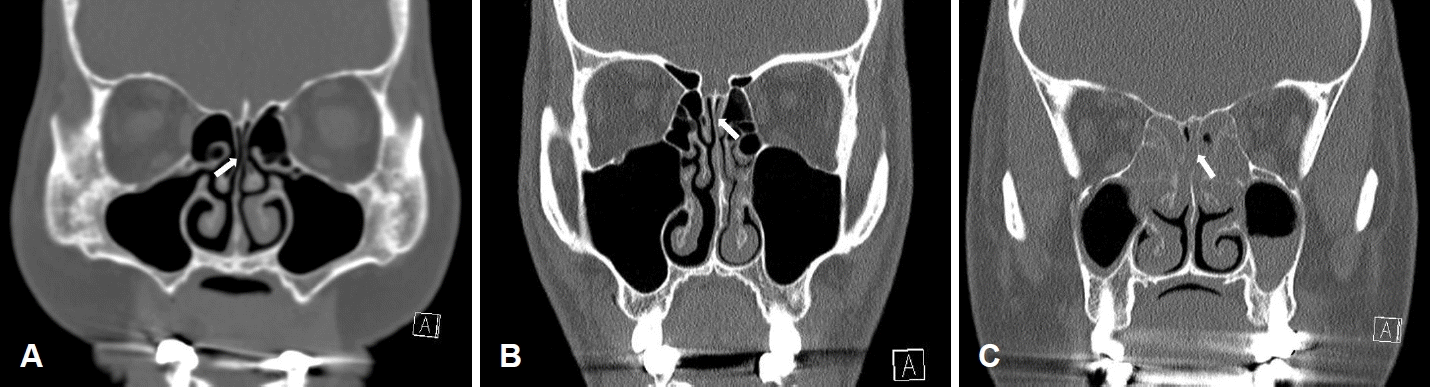

대상 환자의 의무 기록에서 증상 발생 기간, 흡연 여부, 비부비동 질환이나 상기도 감염의 과거력, 증상 발현 전 두부 외상 혹은 뇌수술 여부, 고혈압, 당뇨병, 소화성 궤양 등 기저 질환 여부를 확인하였으며, 신체 검진상 비내시경 소견을 확인하여 비염이나 비용종과 같은 비부비동 질환 유무를 확인하였다. 이전에 무후각증으로 치료를 받았던 경우, 6개월 이내에 스테로이드 치료를 받은 병력이 확인된 경우, 악성종양이나 심근경색과 같은 중증 전신 질환이 확인된 경우 대상에서 제외하였다. 두부 외상이나 뇌수술 병력이 확인된 경우, 알츠하이머병과 같이 후각 중추에 영향을 미칠 수 있는 신경 퇴행성 질환이나 뇌졸중, 뇌출혈 등 신경계 기저질환이 확인된 경우는 중추성 후각장애 가능성을 배제하기 위해 대상에서 제외하였다. 병력에서 확인되지 않은 두개 내 혹은 후구(olfactory bulb) 자체의 외상성 손상이나 종양, 뇌연화증 등 중추 신경계 질환으로 인한 중추성 후각장애 여부와 비부비동 질환 여부를 확인하기 위해 부비강 전산화단층촬영 결과를 검토하였고, 비부비동 상태는 Lund-Mackay 점수로 평가하였다. 후열의 개존 상태는 부비강 전산화단층촬영 관상면에서 양측을 각각 평가하였을 때 후열이 완전히 열려있는 상태를 0점, 부분적인 폐쇄가 관찰되는 경우를 1점, 완전히 폐쇄된 경우를 2점으로 하여 총 0-4점으로 평가하였다(Fig. 1). 부비강 전산화단층촬영에서 종양 혹은 외상이 확인되거나 중추성 후각장애로 판단되는 환자는 대상에서 제외하였다.

Patency of olfactory cleft in coronal scan of paranasal sinus CT. A: Well opened right olfactory cleft (patency of olfactory cleft=0). B: Partially obstructed left olfactory cleft (patency of olfactory cleft=1). C: Totally obstructed left olfactory cleft (patency of olfactory cleft=2). White arrow: olfactory cleft.